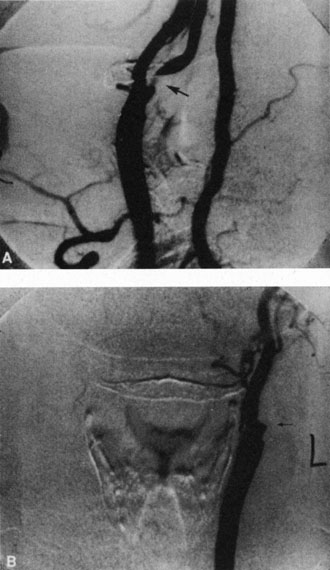

Hypoperfusion retinopathy is characterized by dot and blot hemorrhages in the midperiphery of the fundus, by venous tortuosity and engorgement, by microaneurysms, and by the occasional sludging of blood within the veins. Fluorescein angiography may show areas of capillary nonperfusion; it may also show microaneurysms in the midperiphery and slow arm to retina or arteriovenous transit time (Fig. 9A and 9B).174 The condition does not usually affect the posterior pole, and patients typically have normal visual acuity, although an occasional patient may have macular edema.174 The entire periphery of the eye is usually affected, although there may be more hemorrhages in one quadrant than another. Patients occasionally experience ocular discomfort or eye pain despite normal intraocular pressure. Reduction of the ophthalmic arterial pressure is a pathognomonic feature. Disc edema and disc collaterals are generally not present. The electroretinogram shows abnormalities in both the a- and b-waves (see Fig. 9C).

Fig. 9. Intravenous fluorescein angiogram of a patient with hypotensive or hypoperfusion retinopathy. A: There is a marked delay in the choroidal and retinal filling. B: In the recirculation of the angiogram, there is a characteristic staining of both arteries and veins. C: Electroretinogram shows normal a- and b-waves in the normal right eye (upper tracing) and marked redirection of the a- and b-waves in the affected left eye (lower tracing).